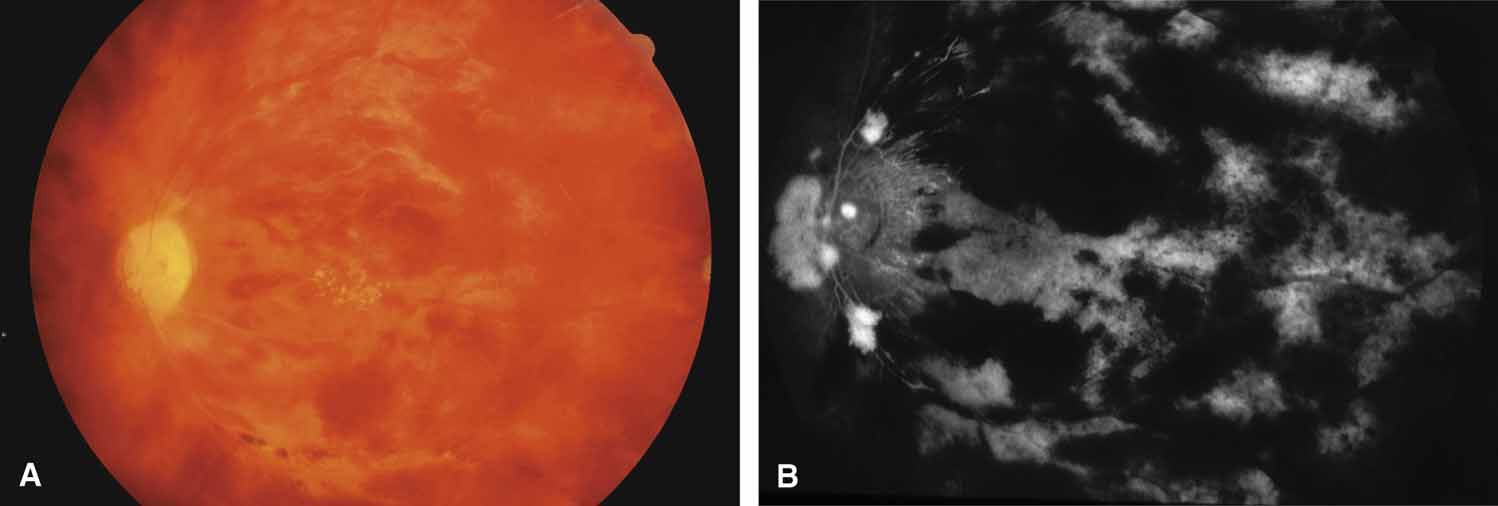

RAISED EPISCLERAL VENOUS PRESSURE

A review of the aqueous blood microcirculation of the eye (Fig. 10) explains how raised venous pressure can affect both retinal vessels and intraocular pressure. From Schlemm's canal, aqueous traverses the intrascleral emissary channels (aqueous veins of Ascher) to the episcleral plexus and then the long ciliary venous vessels. The long ciliary veins, as well as the vortex veins, empty into the ophthalmic vein before entering the cavernous sinus. Increases in episcleral venous backpressure theoretically contribute to a 1:1 mm Hg rise of measured intraocular pressure. The clinical result of an acute rise in external venous pressure may include choroidal effusion, elevated intraocular pressure with blood in Schlemm's canal (Fig. 11), and retinal vein obstruction with intraretinal hemorrhages in a central vein obstruction pattern with or without prominent swelling of the optic nerve. Chronic elevations of venous pressure may permanently damage trabecular meshwork, impairing outflow facility, and result in a chronic open-angle glaucoma.

Obstruction of the venous inflow to the heart may be due to mediastinal tumors, aortic aneurysms, goiters, and enlarged hilar lymph nodes among other causes. A central retinal vein obstruction picture results with engorgement of the retinal veins, peripapillary retinal edema, and elevated intraocular pressure.55 The pressure becomes elevated in the supine position. Correction of the underlying obstruction is ideal, but topical pressure medications may be somewhat effective.

Carotid–Cavernous Fistula

A true shunt between the carotid and cavernous sinusoidal venous system (high-flow type) occurs in 25% of cases and usually results from trauma.56 The more common situation (75% of cases) is a vascular shunt between a dural branch of the external or internal carotid (usually meningohypophyseal branch) and the cavernous sinus (low-flow type).56 There is some evidence that vestigial dural shunts may be congenital and expand when an obstruction occurs in the transverse and sagittal venous drainage systems of the brain.56 The net effect is a direct transmittal of arterial pressure to the retinal and choroidal venous system, which may produce several syndromes. Recent work involving more precise radiologic studies suggests that the specific clinical presentation is determined by the exact location of the vascular anomaly.57 Ocular hypoxia produced by reduced flow may lead to iris neovascularization and glaucoma.58 The more common cause of elevated intraocular pressure is chronic venous pressure elevation that results in permanent damage to the trabecular meshwork. Rarely, vortex venous backpressure may produce choroidal edema, effusion, rotation of the ciliary body, and a congestive glaucoma (Fig. 12).59,60 High- and low-flow arteriovenous shunts pose no threat to human life but have been the object of prodigious surgical efforts. The indications for the surgery should remain intractable eye pain or threatened loss of the eye or other neurological deficits. Shunt flow may be reduced by arterial closure, direct shunt closure, or venous ligation. All these methods, except direct shunt closure, may exacerbate hypoxia and induce iris neovascularization.61